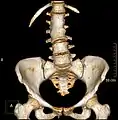

Transitional vertebrae

Short ribs at the first lumbar vertebra, which is thus a transitional vertebra, since lumbar vertebrae normally do not have ribs attached to them.

Transitional vertebrae have the characteristics of two types of vertebra. The condition usually involves the vertebral arch or transverse processes. It occurs at the cervicothoracic, thoracolumbar, or lumbosacral junction. For instance, the transverse process of the last cervical vertebra may resemble a rib. A transitional vertebra at the lumbosacral junction can cause arthritis, disk changes, or thecal sac compression. Back pain associated with lumbosacral transitional vertebrae (LSTV) is known as Bertolotti's syndrome. One study found that male German Shepherd Dogs with a lumbosacral transitional vertebra are at greater risk for cauda equina syndrome, which can cause rear limb weakness and incontinence.[10]